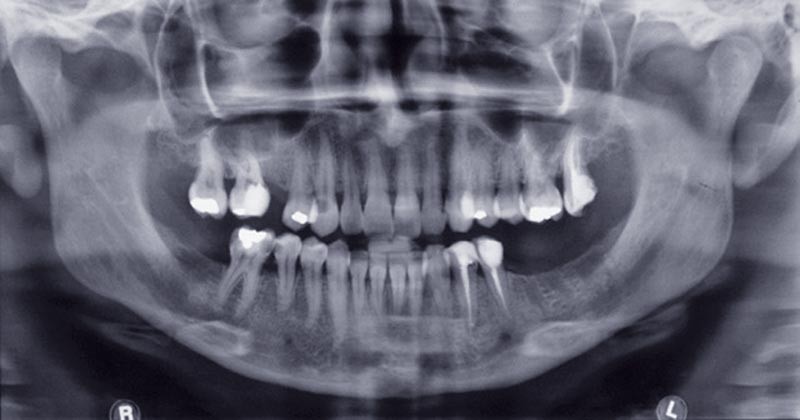

La relation soignant-soigné évolue dans un cadre très particulier, unique et singulier. Ce cadre doit être envisagé dans une dimension éthique, celle du respect de la personne dans sa dignité et son autonomie. En chirurgie dentaire, cette relation s’établit souvent autour de problématiques endodontiques, que ce soit dans le cadre d’une urgence infectieuse ou inflammatoire, de la nécessité de dépulper ou non, de la possibilité de conserver une dent ou non. Elles sont au carrefour de décisions et d’actes touchant au corps du patient. Quand les conditions le permettent, le traitement envisagé sera conservateur et respectueux de l’intégrité physique du patient.